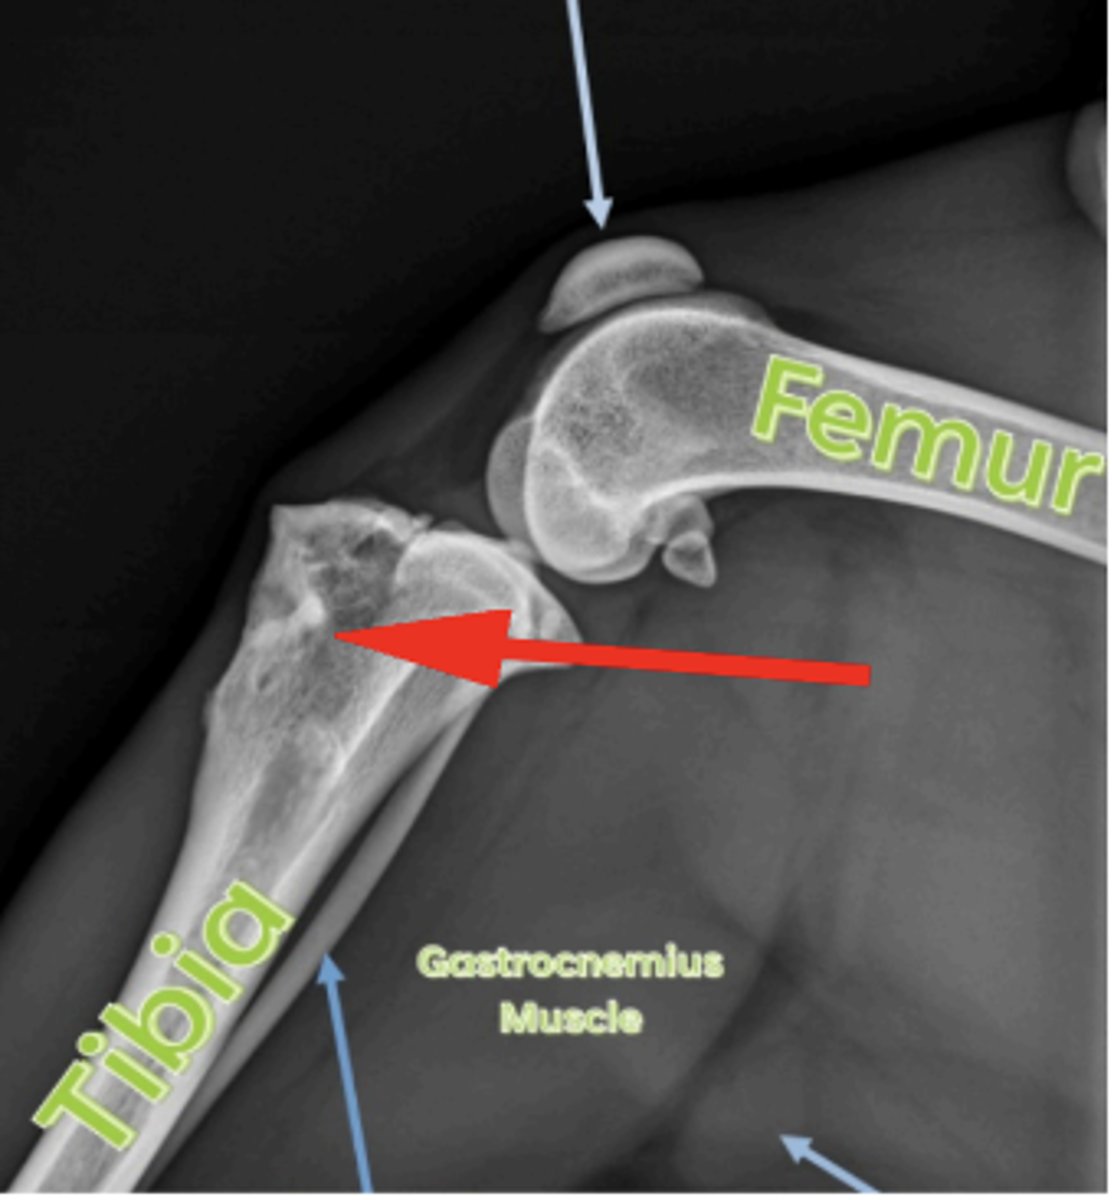

Medial femoral epicondyle

3 y/o horse lameness, effusion of stifle, where is the cyst?

Mineralized cartilaginous flap

What is a Common finding of OCD?

Flat femoral head

What is the most common finding of OCD in dog shoulder?